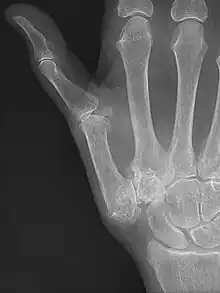

Diagnosis

TMC OA is diagnosed based on symptoms and signs.[8] Radiographs can confirm the diagnosis and the severity of TMC OA. Other diagnoses in this region include scaphotrapezial trapezoid arthritis and first dorsal compartment tendinopathy (De Quervain syndrome) although these are usually easy to distinguish.

TMC OA severity was classified by Eaton and Littler which can be simplified as follows:[21][22]

Stage 1:

- slight widening of the joint space

- < 1/3 subluxation of the joint (in any projection)

Stage 2:

- Osteophytes, < 2 mm in diameter, are present. (usually adjacent to the volar or dorsal facets of the trapezium)

Stage 3:

- Osteophytes, > 2 mm in diameter, are present (usually adjacent to the volar and dorsal facets of the trapezium)

- Slight joint space narrowing

Stage 4:

- Narrow joint space

- Concomitant scaphotrapezial arthritis

A simpler classification is no arthritis, some arthritis, and severe arthritis.[23] This simpler classification system omits the potentially contradictory details of the Eaton/Littler classification and keeps scaphotrapezial arthrosis separate.